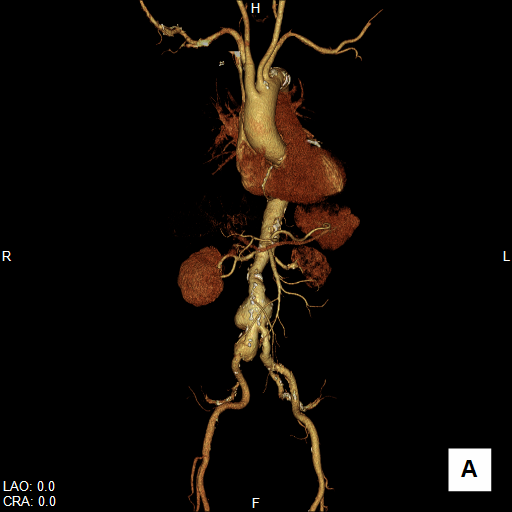

大動脈疾患の診断では、①瘤/解離の範囲と位置、②血流評価、③主要分枝・周囲臓器との関係、④並存疾患の評価、⑤ステントグラフト治療の可能性評価などが必要です。

CTは、体軸方向に分解能の高いボリュームデータを短時間かつ広範囲に得ることができるので、体軸方向に広いスキャンが必要な大動脈疾患の検査に適しています。大動脈病変と分枝動脈の関係だけでなく、分枝動脈自身の評価も可能ですから、手術前シミュレーションや、インフォームドコンセントの参照画像にも有用です。

腹部大動脈瘤へのステントグラフト内挿術評価CT

大動脈解離へのステントグラフト内挿術評価CT